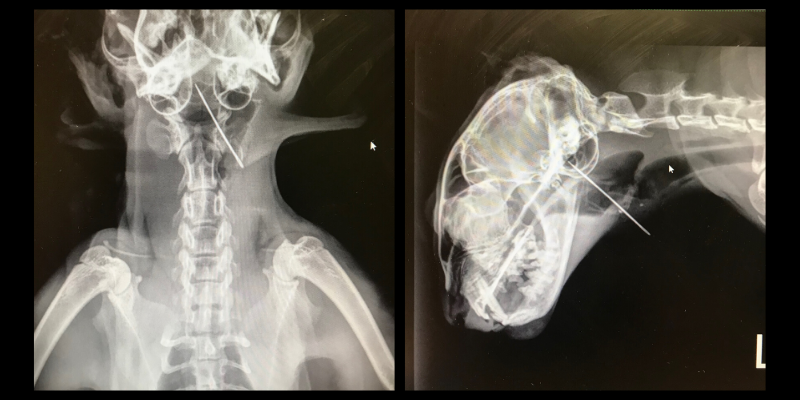

When Scooter arrived, she was swallowing hard and her breathing was not quite normal. Our emergency team could feel the needle in her upper neck, but an entry wound was not obvious. The needle was visible, however, on radiographs (seen in the image below). Since it could be felt easily, our emergency veterinarian recommended that Scooter be sedated and medicated for pain in preparation to have the needle surgically removed. Of course, Scooter’s owner agreed.

In Scooter’s neck, our team found a two-inch needle (plus thread!) Upon waking, she already appeared more comfortable, and she was sent home that day with antibiotics and pain medications.